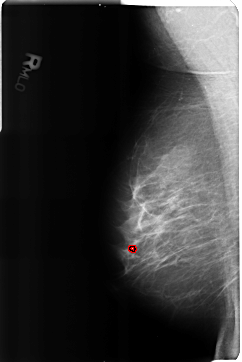

B_3207_1.RIGHT_MLO

RIGHT_MLO LINES 4696 PIXELS_PER_LINE 3136 BITS_PER_PIXEL 12 RESOLUTION 50 OVERLAY

FILE: B_3207_1.RIGHT_MLO.OVERLAY

TOTAL_ABNORMALITIES 1

ABNORMALITY 1

LESION_TYPE CALCIFICATION TYPE LUCENT_CENTER DISTRIBUTION N/A

ASSESSMENT 2

SUBTLETY 5

PATHOLOGY BENIGN_WITHOUT_CALLBACK

TOTAL_OUTLINES 1

BOUNDARY